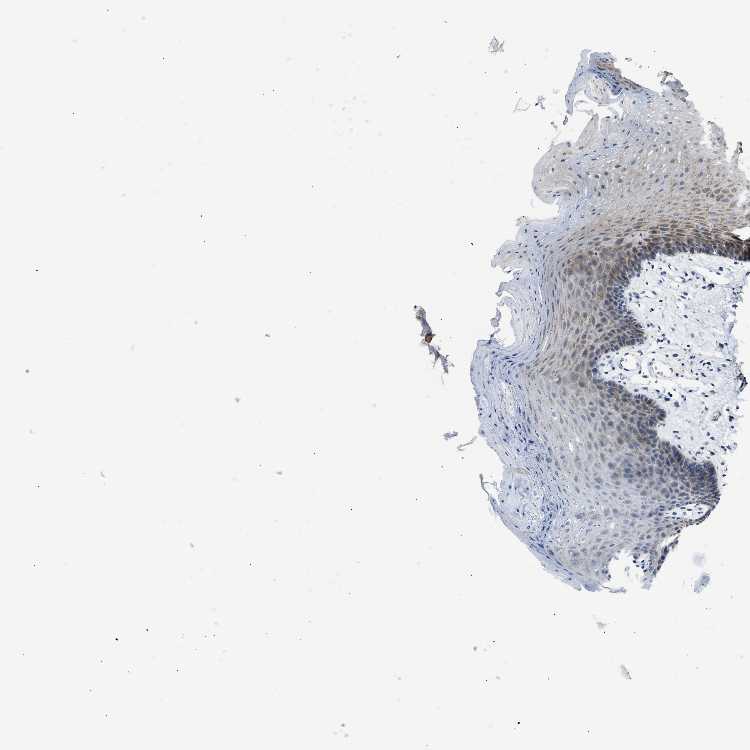

TISSUE PRIMARY DATA ORAL MUCOSA Show tissue menu

ORAL MUCOSA - Antibody stainingi

Antibody staining in the annotated cell types in the current human tissue is reported as not detected, low, medium, or high, based on conventional immunohistochemistry profiling in selected tissues. This score is based on the combination of the staining intensity and fraction of stained cells.

Each image is clickable and will lead to virtual microscopy that enables deeper exploration of all samples and also displays staining intensity scores, fraction scores and subcellular localization as well as patient and tissue information for each sample.

Antibody CAB019309

Squamous epithelial cells Medium